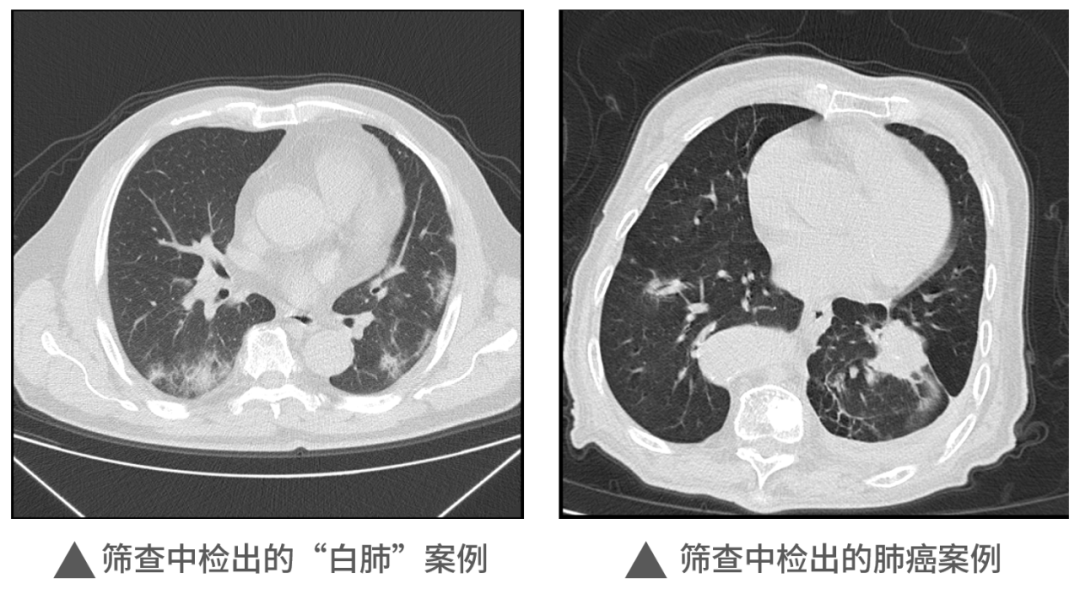

本次活動中,明峰醫(yī)療移動CT充分展現(xiàn)了它的適應性和便利性,在近1000人的檢查中,共查出肺部炎癥300余例,肺部結節(jié)560例,同時檢出一例肺癌病例。這對于本次篩查人員今后胸部健康和治療提供了重要的參考和指導,為全區(qū)居民和企業(yè)提供了堅實的保障,同時大大提升區(qū)內的醫(yī)療健康保障能力。未來,明峰醫(yī)療醫(yī)療仍將持續(xù)致力于高端醫(yī)療設備的普惠應用。作為杭州市錢塘區(qū)的區(qū)內企業(yè),將沿著區(qū)委區(qū)政府“四個全域”建設的發(fā)展規(guī)劃和區(qū)衛(wèi)健系統(tǒng)提出的目標及要求,發(fā)揮人才企業(yè)的優(yōu)勢,以科技創(chuàng)新引領企業(yè)發(fā)展,為區(qū)內產城融合的服務配套做好應有的保障和支撐工作,探索政產學研合作的新思路新模式,共建共享,共同成長,造福更多的人民百姓,在書寫中國式現(xiàn)代化的錢塘答卷上也添上濃墨重彩的一筆。